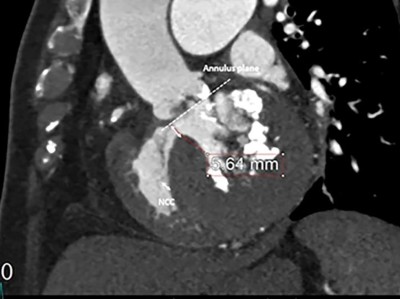

Chirurgische Transkatheter-Aortenklappenexplantation

• TAVI

• Übersichtsartikel

Mit dem rasanten Anstieg der Transkatheter-Aortenklappenimplantationen (TAVR) ist auch die Zahl der notwendigen Reinterventionen stark gewachsen. Insbesondere die herzchirurgische Explantation von TAVR-Prothesen (engl. Explant-TAVR) entwickelt …

Transkatheter Aortenklappenimplantation (TAVI)/© Boonyakiatwattana W. et al. doi.org/10.1186/s12872-022-02576-y unter CC-BY 4.0, Echokardiografie der Aortenklappe/© Pitchy / stock.adobe.com, Schmerzende livide Areale am Bauch/© A. Frahnert, Aneurysma bei 2-monatigem Säugling mit Kawasaki-Syndrom/© Navidi et al. https://doi.org/10.1186/s13256-024-04987-1 unter CC-BY 4.0, Kanüle für Katheterbehandlung/© romaset / stock.adobe.com, Ärztin führt eine Nierenultraschalluntersuchung durch/© Graphicroyalty / stock.adobe.com (Symbolbild mit Fotomodell), Patient mit perforierter ICD-Tasche/© P. Fleckenstein, Vegetationen der Herzklappe/© Schönfeld L et al. / all rights reserved Springer Medizin Verlag GmbH, Echokardiografische Evaluation der Aortenklappeninsuffizienz/© Digitales Archiv der Uniklinik Köln, Explantierte Prothese nach Transkatheter-Aortenklappenimplantation/© Saha S et al. / all rights reserved Springer Medizin Verlag GmbH, Mitralklappe/© Springer Medizin, Hauteffloreszenzen der rechten Hand/© Marschner M et al. / all rights reserved Springer Medizin Verlag GmbH, Search Icon, Eine ältere Frau riecht an einem Basilikumblatt/© Halfpoint / Stock.adobe.com (Symbolbild mit Fotomodell), Ultraschall bei einem älteren Patienten/© Alex Potemkin / Getty Images / iStock (Symbolbild mit Fotomodellen), Person hält Tablette und Glas/© bilderstoeckchen / stock.adobe.com (Symbolbild mit Fotomodell), EKG befunden mit System - EKG Essential/© Springer Medizin Verlag GmbH